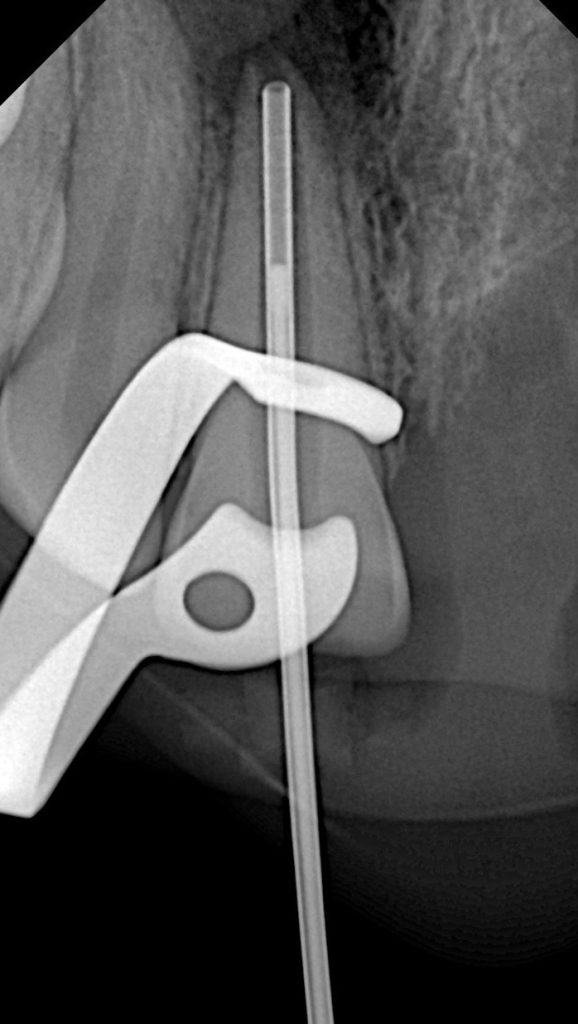

Radiographic Findings:

•Blunderbuss canal

•Thin dentinal walls

•No apical constriction

•Mild periapical changes suggestive of inflammatory root resorption

Step 2 – Canal Preparation

Working length established using apex locator and radiograph. Gentle canal debridement performed using 2.5% NaOCl irrigation to avoid extrusion beyond immature apex. Minimal instrumentation due to fragile dentinal walls.